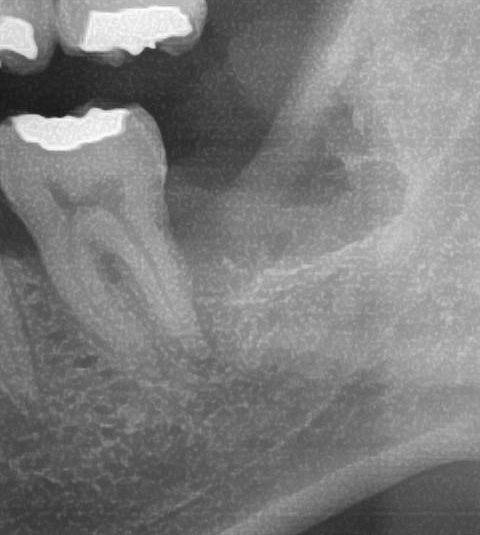

次にパノラマ写真を撮影してみると、左下の親知らずは歯茎の中で、手前の歯を押すように真横に生えているのが確認できました。